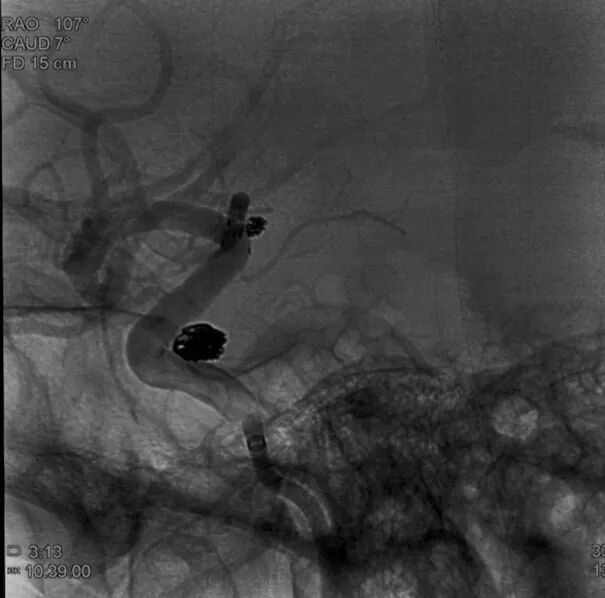

通过璞慧0.017微导管填入Target 1.5/2弹簧圈部分成篮,后释放Atlas 3.0/15支架覆盖瘤颈处,继续填入弹簧圈时微导管脱出,尝试用弹簧圈将微导管引导超选瘤腔失败。

撤出弹簧圈,Asahi 0.014微导丝引导璞慧 0.017微导管穿支架网孔进入动脉瘤内。

继续填入Target 1.5/2弹簧圈成篮,后完全释放支架,其近端位于颈内动脉分叉处,远端位于A1远端。

填入第一枚弹簧圈

通过调整栓塞微导管的张力继续填入Target 1/3弹簧圈。